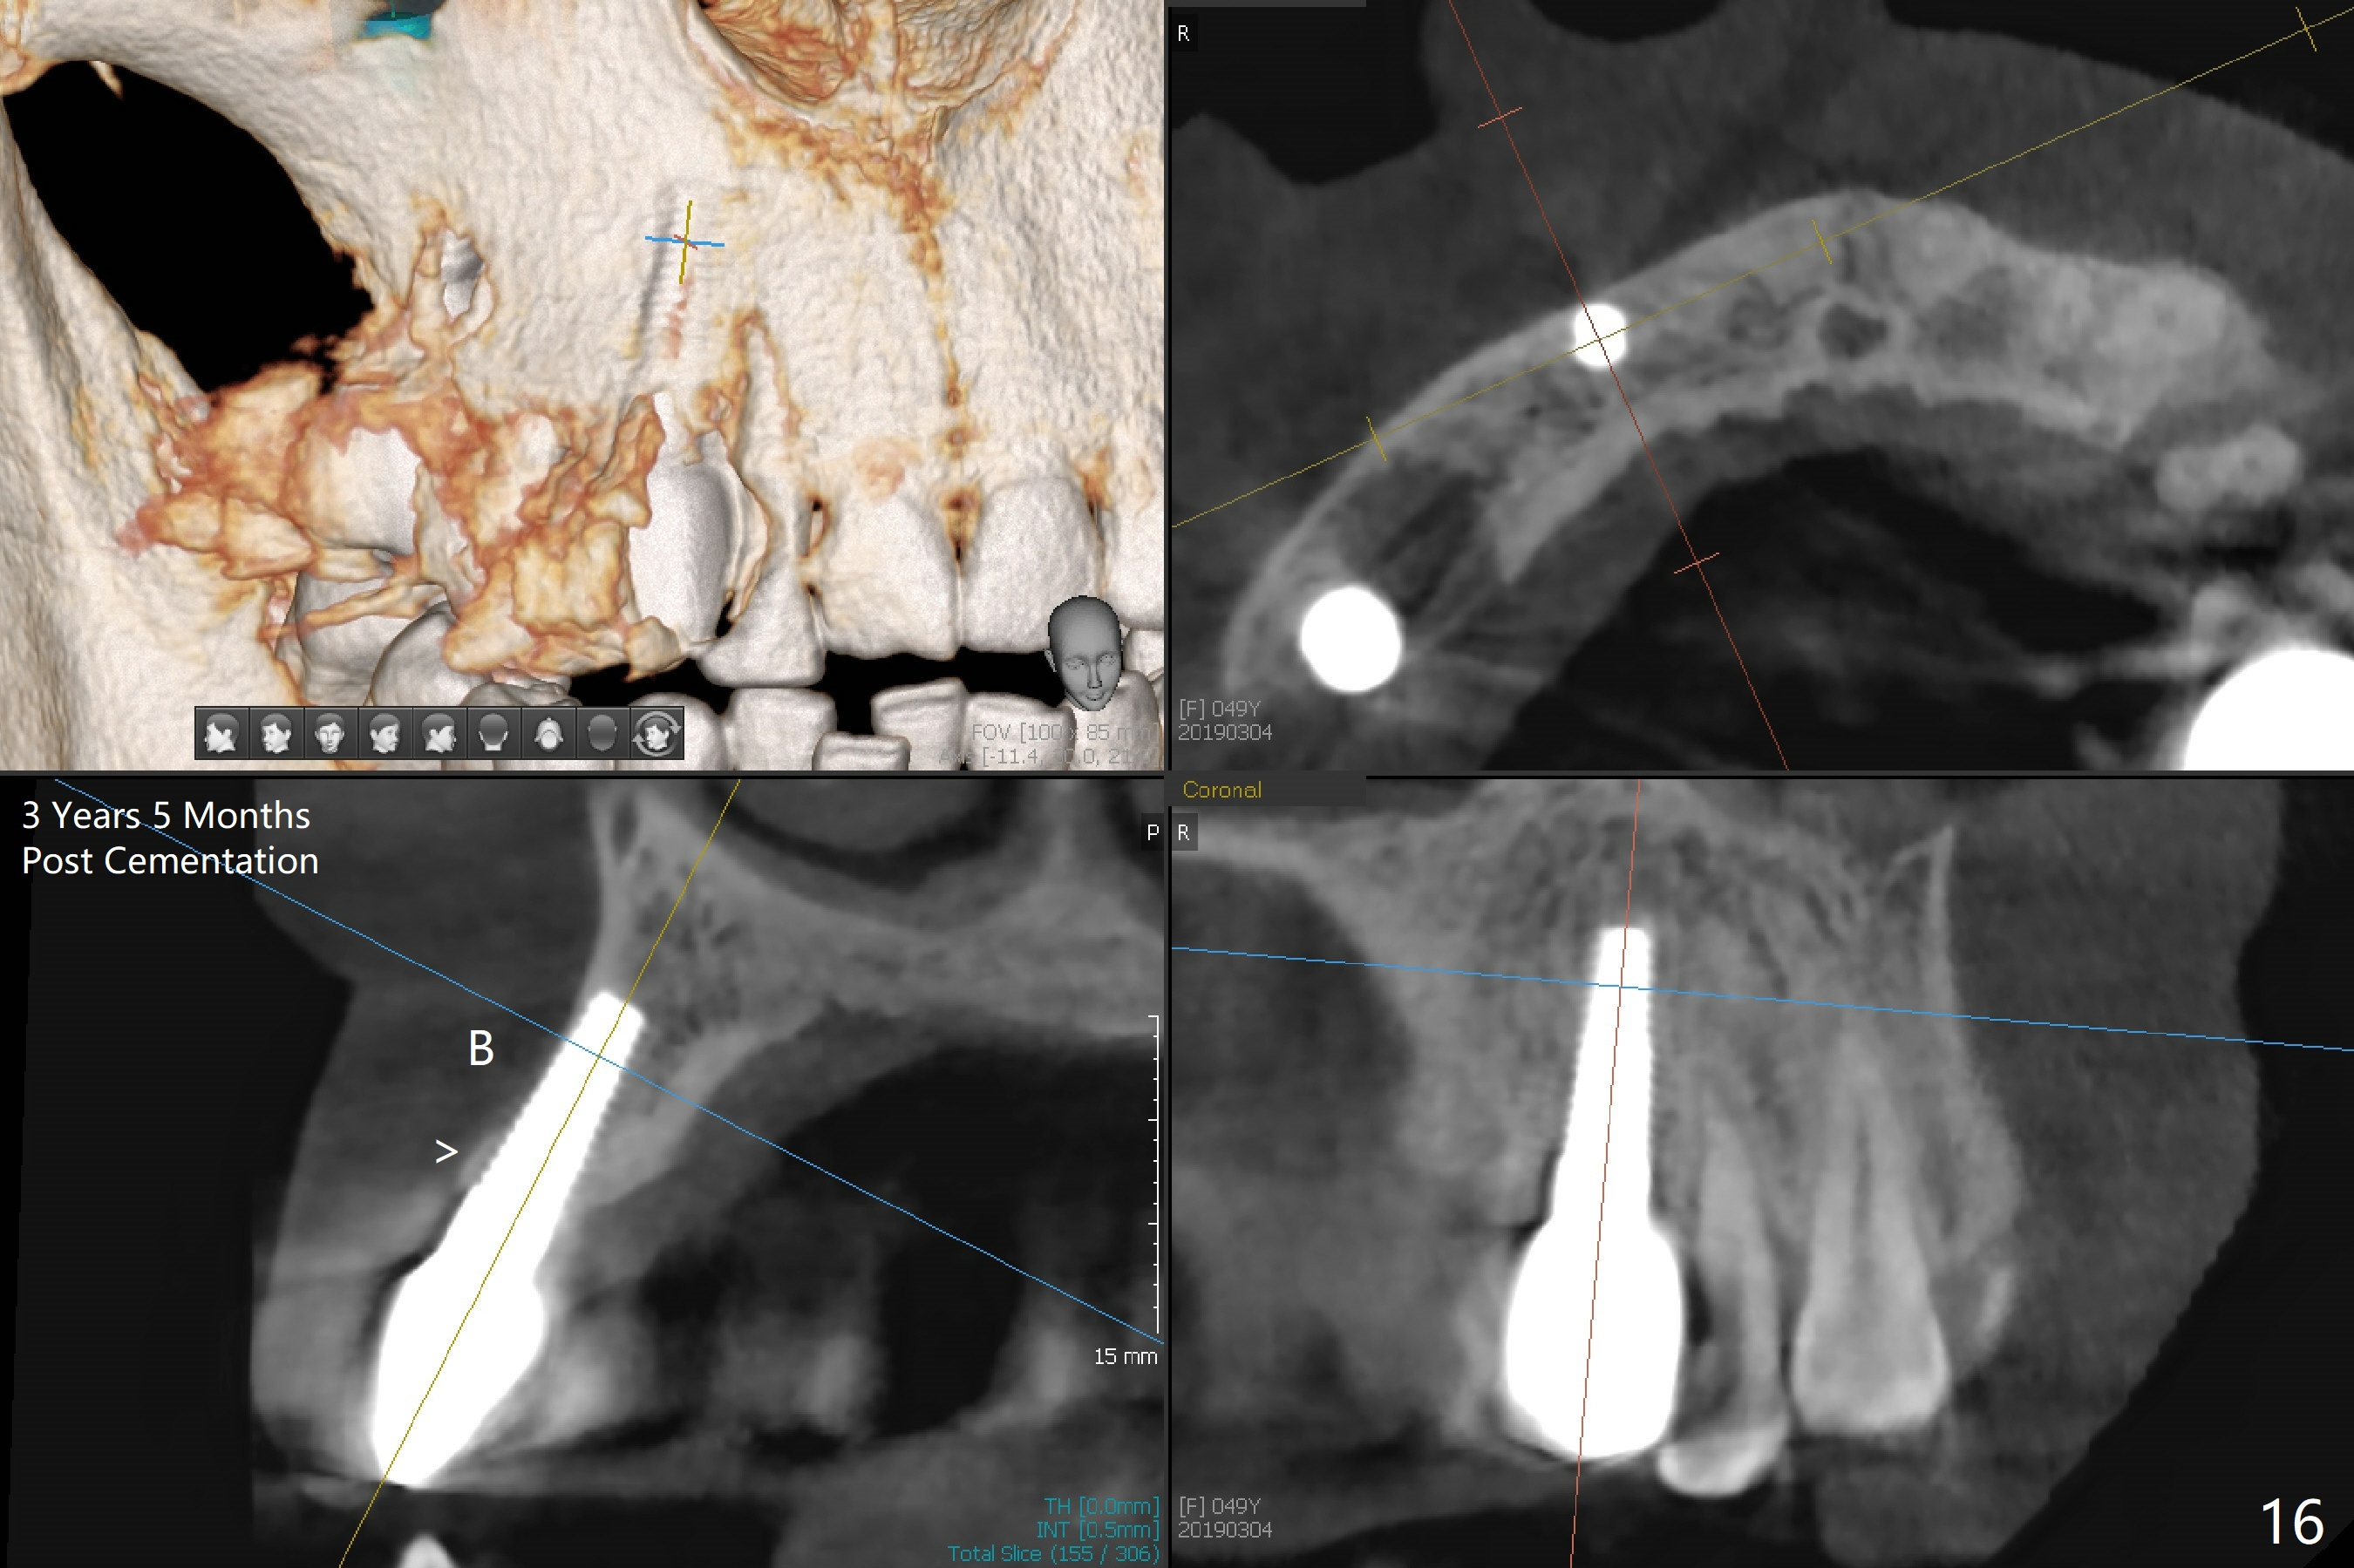

Four months post implant placement, the immediate provisional (Fig.1 P) has mobility with tenderness and perforation at the cervix (^). When the provisional is removed, the buccal plate bulging is more evident (Fig.2 arrowheads). The latter is apparently caused by bone expansion associated with implant placement (Fig.3 black *), since the bulging is not so obvious in a preop CBCT 3 D image (Fig.4 *). There is a layer of fiber granulation tissue (Fig.3 white *) around the mobile implant (I). More fiber tissue is noted when the implant is removed (Fig.5). A new osteotomy is created in the palatal wall of the existing implant site with 2 mm pilot drill, followed by 2.5 and 3 mm reamers. As a 4.5x17 mm tap is being inserted (Fig.6 T), it is deviated buccally. Reamers are re-used to try to remove more palatal bone to let the implant be placed more palatally. When a 4.5x17 mm tissue-level implant is placed (Fig.7,8 I with insertion torque >60 Ncm), there is a small buccal gap (Fig.8 *). A 20° angled abutment (Fig.7,8 A) is placed. An immediate provisional is fabricated with cosmetic satisfaction.

The gingiva is healthy 6 months postop (Fig.13) without buccal plate collapse (Fig.14). The implant and abutment have been prep for final restoration (Fig.15). Although the buccal plate is thin 3 years 5 months post cementation (Fig.16 B), the crest (>) is present, which accounts for no periimplantitis.